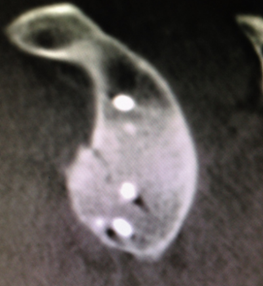

肩关节Bony-Bankart损伤

肩关节镜下缝合修复Bony-Bankart术后